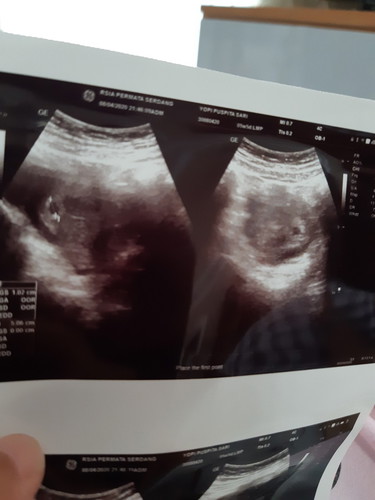

Allhamdulillah saya positif hamil , sekarang usia kehamilan saya 5minggu 5hari , kemarin sudah di usg , terlihat kantung nya , namun janin nya belum terlihat ? Diusia kehamilan berapakah janin akan terlihat , mohon jawabanya yaa